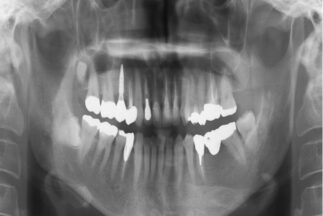

- Before

| 治療内容 | 上顎右側5相当部へインプラント埋入と同時にチタンメッシュを用いて自家骨と骨補填材による骨増生術を行った |